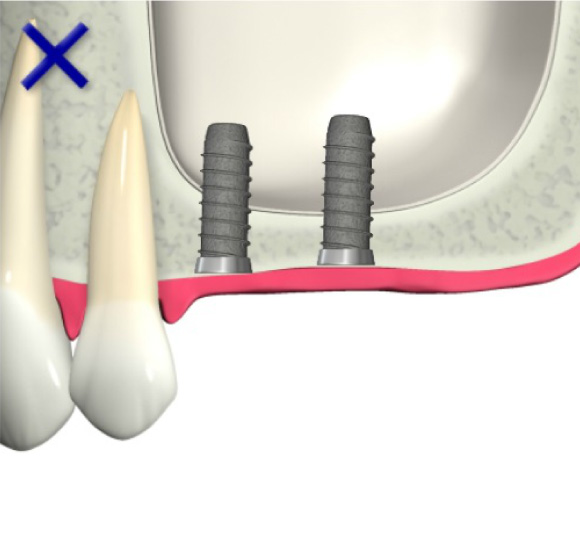

骨が少ない場合①

歯槽骨が吸収し、上顎洞が下がっています。このままではインプラントが突き抜けてしまうためインプラントはできません。

インプラントを支えるための歯槽骨が十分でないためインプラントはできません。

インプラントを支えるための歯槽骨が作られました。インプラントを埋入する事が出来ます。